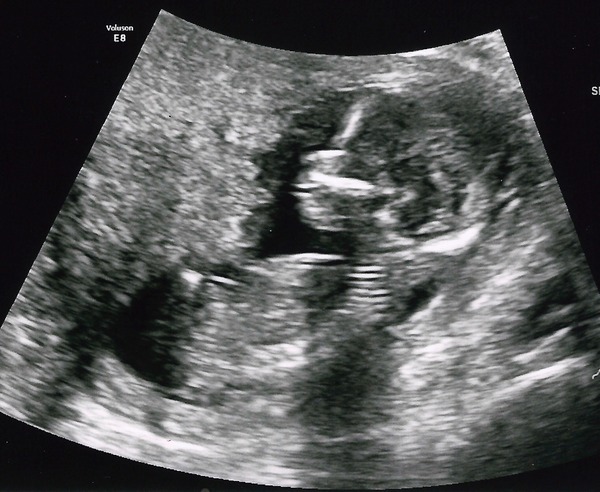

Fizzyboo · 09/02/2016 19:50

The sonographer said everything looked 'perfect' though and said the quad test is still good, just a tiny bit less than the combined, but not to worry.

I asked her about the visual identifiers such as the nasal bone, she said she could clearly see a nasal bone. (Prob got my nose then not my DH's button nose Wink)

Baby was in an annoying position and I had to lie on my side for a bit and cough to make them wriggle into a new shape!

Here's my pic, obviously now dated as 14+3